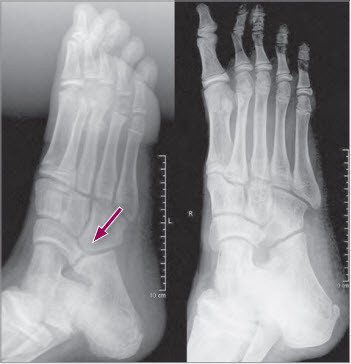

Hierbei zeigt sich bei der Coalitio calcaneonaviculare häufig sehr klar die typische Verbindung zwischen dem vorderen Calcaneus- und dem lateralen Naviculareanteil im Röntgenbild (Schrägaufnahme – Abb. 2).